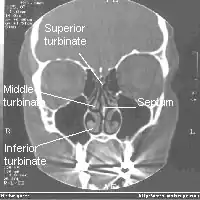

Les cavités nasales ou fosses nasales sont deux espaces séparés par une cloison : le septum nasal. Elles sont situées :

Il y a trois cornets dans chaque cavité nasale :

- le cornet inférieur : le plus grand, aussi long que l'index;

- le cornet moyen : aussi long qu'un auriculaire ;

- le cornet supérieur : très petit.

Les deux cavités nasales sont séparées par la cloison nasale appelée septum.